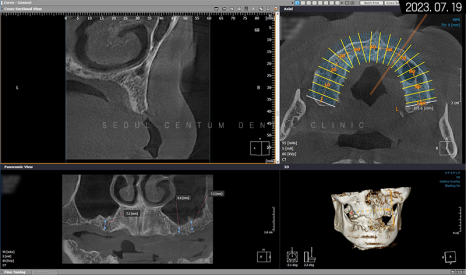

그래서 아래턱을 보존할 수 없는 영구치를 먼저 발치하고 임시 틀니를 사용하면서 저작 기능을 갖기로 했죠. 상악은 픽스처를 고정했고 위턱뼈 어금니 위의 상악동막이 내려왔기 때문에 측방 상악동 거상술도 시행해야 했습니다. 나머지 치조체는 픽스처 고정 위치에 따라 치조정 술식으로 뼈이식재를 넣기로 했습니다.

위턱뼈의 1차 인공 치근 식립을 마치고 나서 3~4개월 후 2차 힐링 어버트먼트를 연결하기로 했으며 동시에 아래턱도 자가골 유도 재생이 어느 정도 진행되었기에 필요시 치조골 이식과 함께 픽스처를 고정해서 1차 수술을 마무리하기로 했습니다.

그렇게 약 9개월의 전체임플란트 기간을 들여서 완성된 모습을 만날 수 있었는데요. 골융합을 높이기 위해 네오 브랜드와 폰틱을 결합하여 사용했습니다.

임플란트 풀케이스는 환자분의 치조체 상태가 중요하며 픽스처 고정도 6~9개까지 골 소실 여부, 개인 필요도 등에 따라 적용할 수 있기에 정확한 검사와 판단이 요구되는 술식입니다. 또한 폰틱 보철물로 수복하기에 위턱과 아래턱의 각도와 교합 상태를 정확히 확인하고 고려해서 폰틱 제작에 들어가야 하는데요. 만일 약간이라도 측정 범위가 어긋나면 저작 기능이 불편해질 수 있으므로 정교하게 설계해서 보철물을 만들어야 합니다.

또, 픽스처가 잇몸뼈 밖으로 돌출되지 않도록 식립해야 하며 어버트먼트도 잇몸에 밀착될 수 있도록 결합해야 하고 폰틱을 수복할 때는 생물학적 폭경까지 고려하면서 진행해야 합니다.